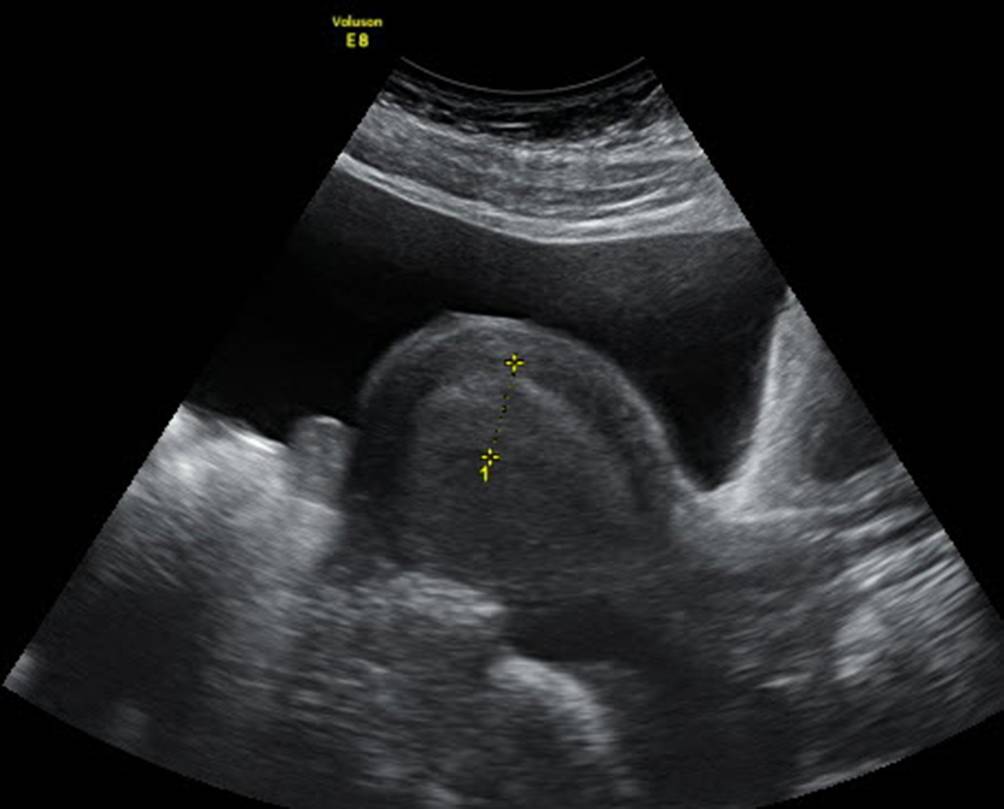

Abb. 4

Uterus bei 14-jähriger Patientin in der zweiten Zyklushälfte mit ausreichender Blasenfüllung. Das Endometrium ist mit 9 mm gemessen